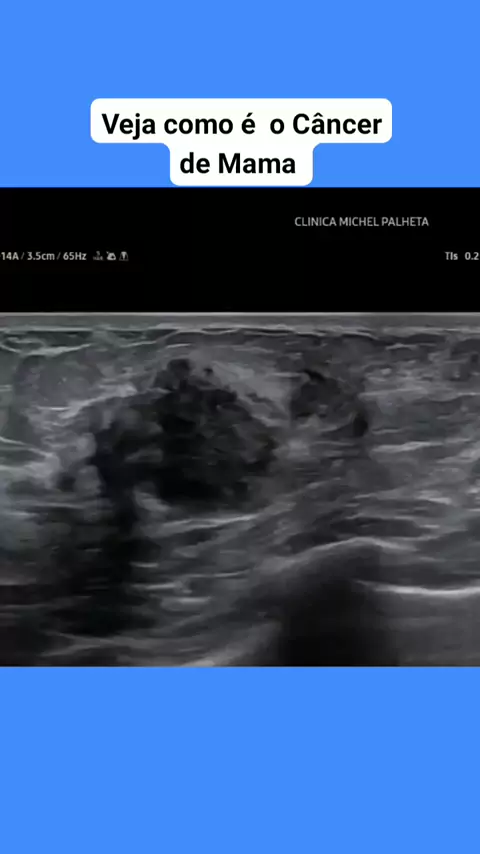

Veja como é o é Câncer de Mama #medicina #medico #parto #recemnascido #Saúde